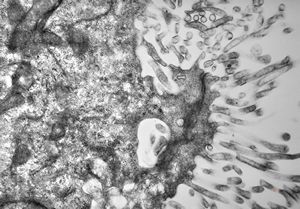

M,1y. | plexus papilloma

M,1y. | plexus papilloma

M,1y. | plexus papilloma

M,1y. | plexus papilloma

M,3y. | plexus papilloma

M,1y. | plexus papilloma

M,1y. | plexus papilloma- solitary kinocilium